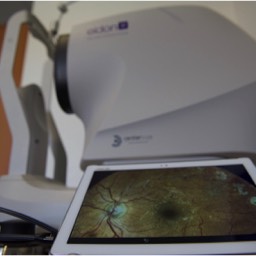

Ci-dessous on voit des néovaisseaux dus à une Dégénérescence Maculaire Liée à l'Age (DMLA). Les rétinophotographies sont réalisées avec l'appareil Eidon de la société italienne CenterVue, et l'OCT angiography est réalisée avec l'OCT de la société américaine Optovue.

Déplacez à la souris la tirette vers la gauche ou la droite, ce qui permet de comparer la vue en couleurs et l'emplacement des néovaisseaux choroidiens.